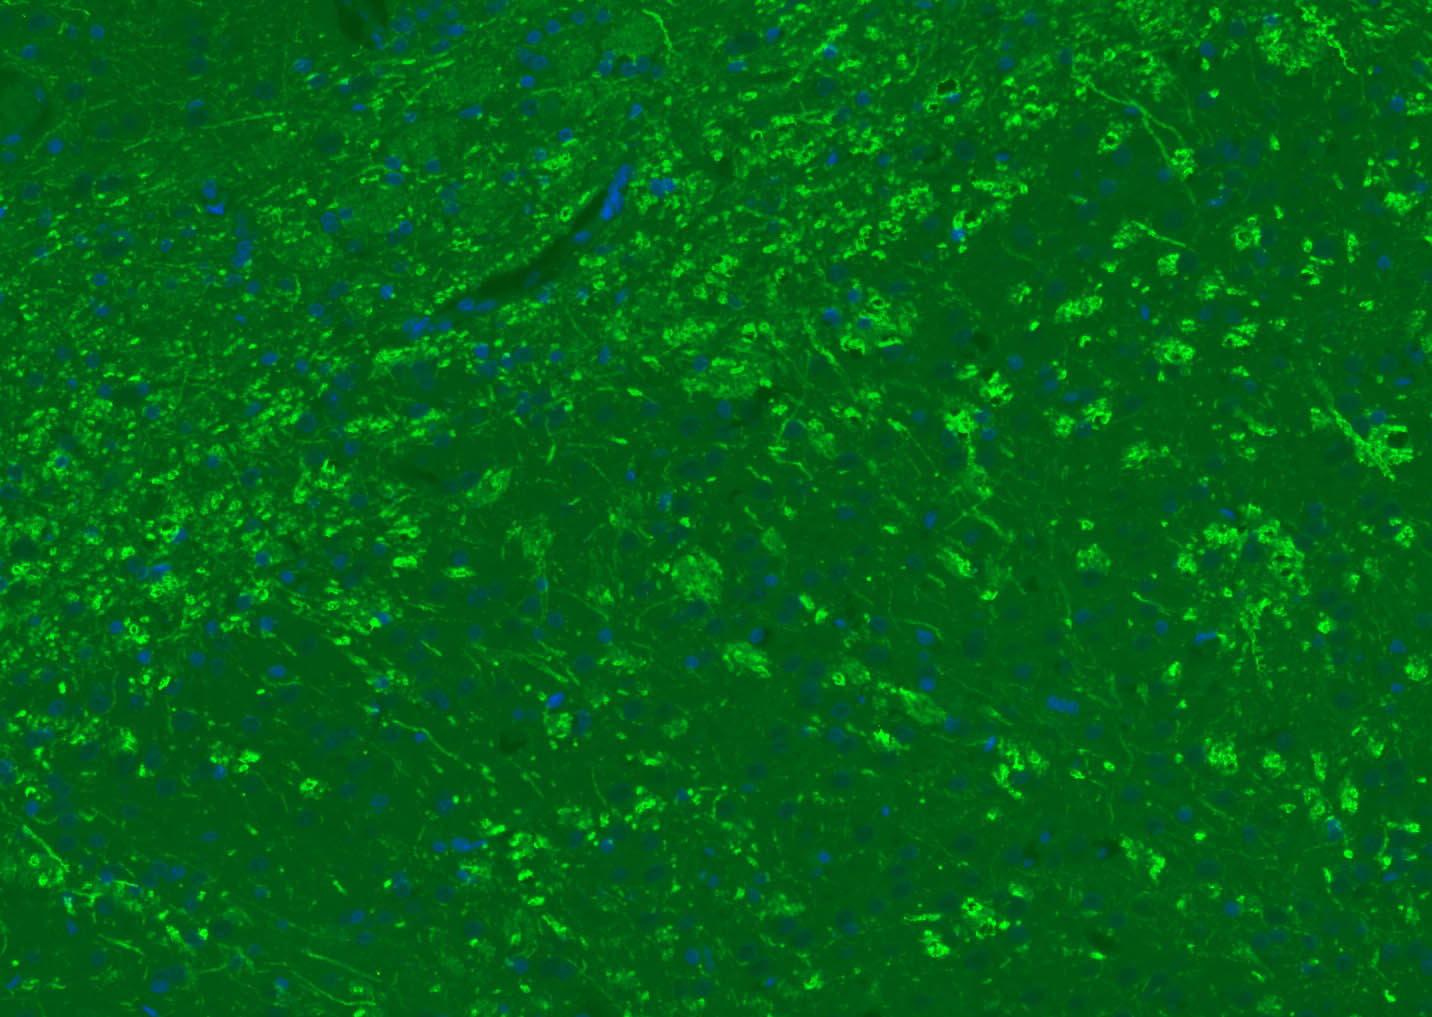

| 背景资料 | Oligodendrocyte Marker The classic group of Myelin basic protein (MBP) isoforms (isoforms 4 to 14) are with PLP the most abundant protein components of the myelin membrane in the CNS. They have a role in both its formation and stabilization. The smaller isoforms might have an important role in remyelination of denuded axons in multiple sclerosis. The non classic group of MBP isoforms (isoforms 1 to 3/Golli MBPs) may preferentially have a role in the early developing brain long before myelination, maybe as components of transcriptional complexes, and may also be involved in signaling pathways in T cells and neural cells. Differential splicing events combined to optional posttranslational modifications give a wide spectrum of isomers, each of them having maybe a specialized function. |

| {IF} | {1:500-2000} |

[IF={{ 7.59 }}] {Yuanxin Zhai. et al. High-efficiency Brain-targeted Intranasal Delivery of BDNF Mediated by Engineered Exosomes to Promote Remyelination. BIOMATER SCI-UK. 2022 Aug;:} {IF} {Mouse}